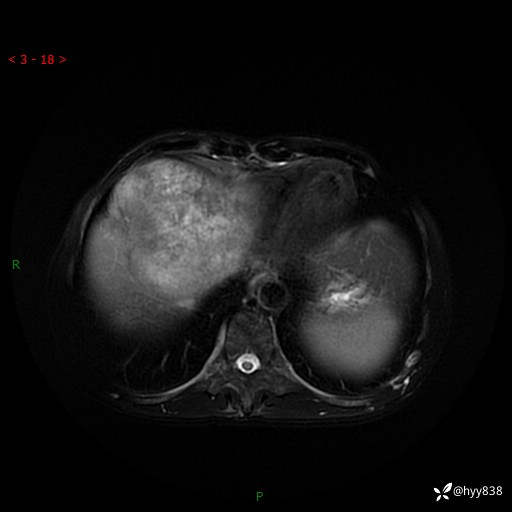

【患者信息】:58岁/男

【主诉】:发现肝占位2天

【现病史及既往史】:患者2天前于当地市第五医院查上腹部磁共振提示:肝脏S4段占位性病变,肝ca可能,胆囊结石,腹膜后多发肿大淋巴结,无剑突下及右上腹疼痛不适,无明显反酸、嗳气,无畏寒、头晕、头痛,无尿频、尿急、尿痛等不适,今为求进一步治疗特来我院就诊,门诊以“肝占位”收住我科。 患者病程中精神、睡眠、饮食尚可,大小便正常、体力体重无明显变化

【检查】:肝脏MRI】平扫+增强